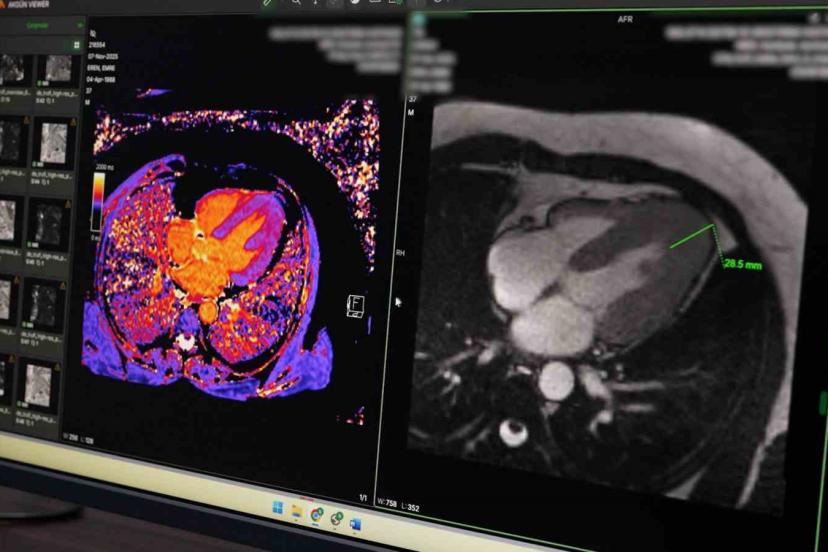

Hastanede uygulanan koroner BT anjiyografi yöntemiyle kalp damarlarının girişimsel işleme gerek kalmadan görüntülenebildiğini belirten Petik, bu sayede hastaların klasik anjiyografi öncesinde detaylı şekilde değerlendirilebildiğini ifade etti. Yeni başlatılan kardiyak MR uygulamasının da kalp kası ve kapak hastalıklarının tanısında önemli katkı sunduğunu dile getirdi.

Örnek bir vakaya da değinen Petik, kardiyak MR sayesinde nadir görülen bir kalp kası hastalığının erken dönemde tespit edilerek hastaya uygun tedavi planlamasının yapıldığını ifade etti. Petik, yapılan yatırımlar ve güçlü teknik altyapıyla Malatya Eğitim ve Araştırma Hastanesi’nin ileri görüntüleme alanında bölgesel merkez olma yolunda önemli mesafe kat ettiğini belirterek, vatandaşların başka illere gitmeden nitelikli sağlık hizmetine ulaşmasının hedeflendiğini söyledi.